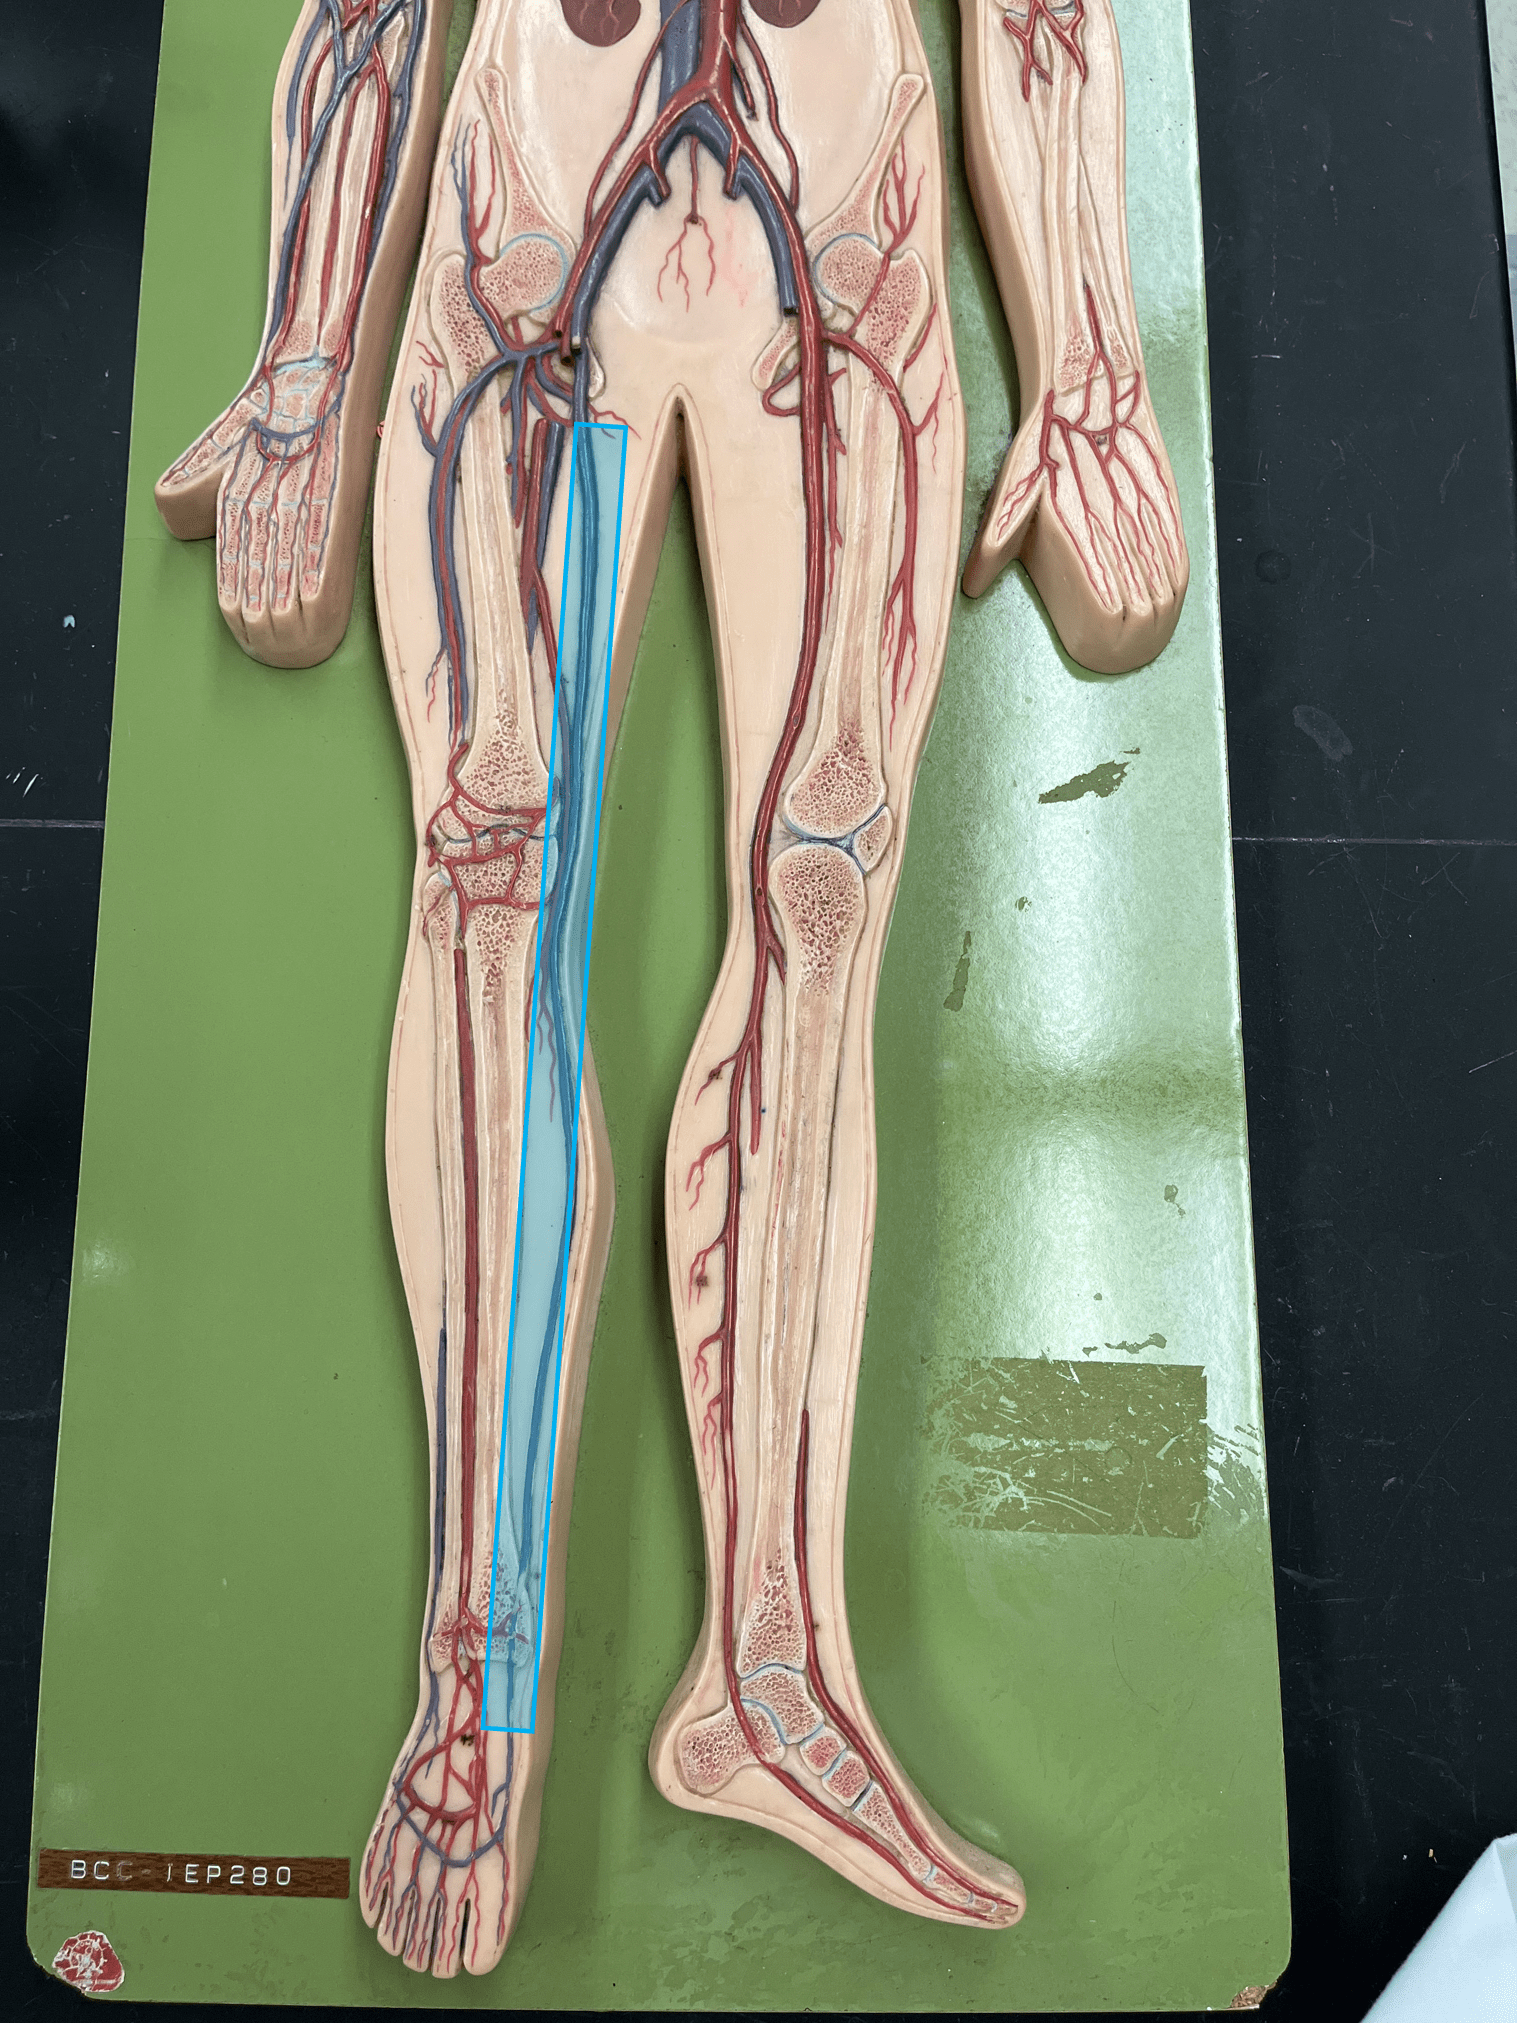

• An artery of the head and neck.

• Originates from the brachiocephalic trunk (R.) or the aortic arch (L.).